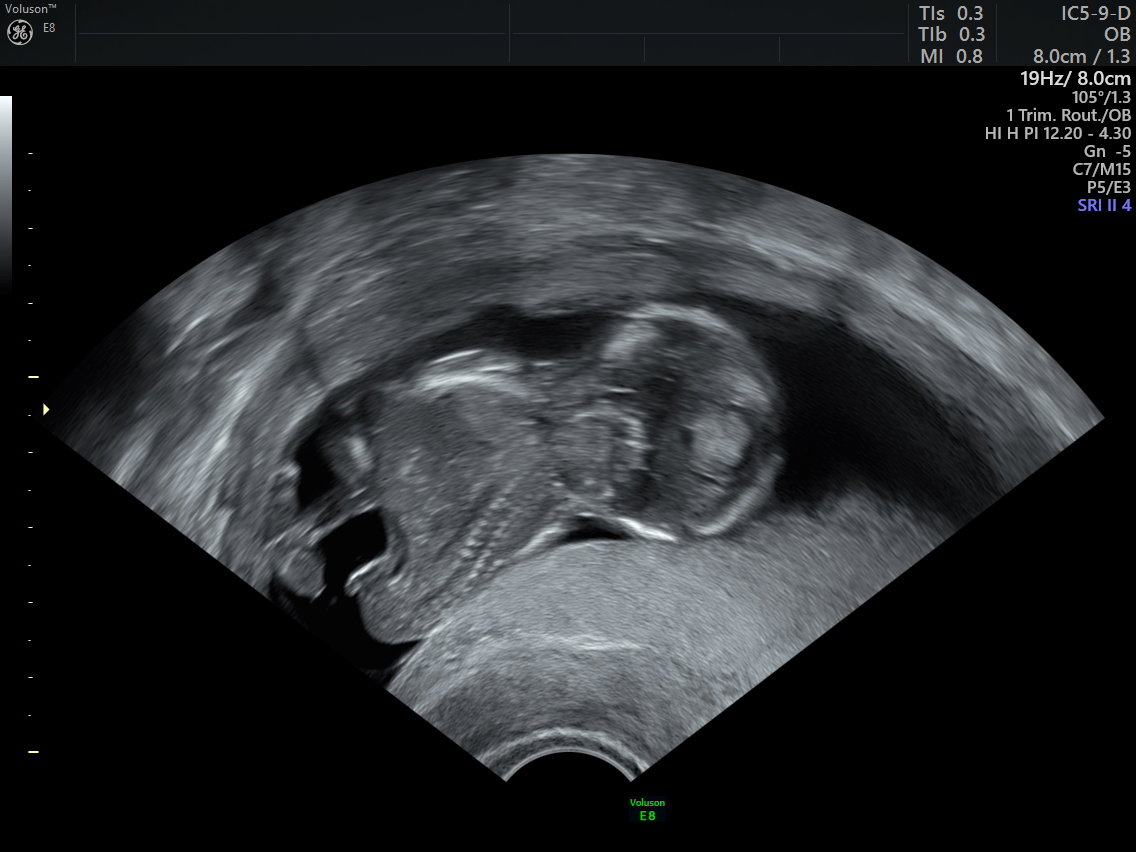

Rahim filmi, rahim iç boşluğunu ve tüplerin açıklığını değerlendirmek için yapılan özel bir röntgen görüntüleme yöntemidir.

Bu işlem sırasında rahim içine kontrast madde verilir ve röntgen altında görüntü alınır. Eğer tüpler açıksa kontrast tüplerden karın içine yayılır. Eğer tıkanıklık varsa kontrast ilerlemez ve bu durum net şekilde görülür.